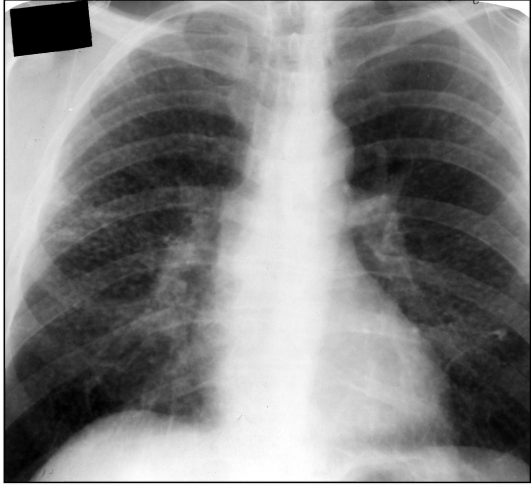

Рентгенологические изображения и синдромы патологии легких

Раздел: Кадры-подсказки